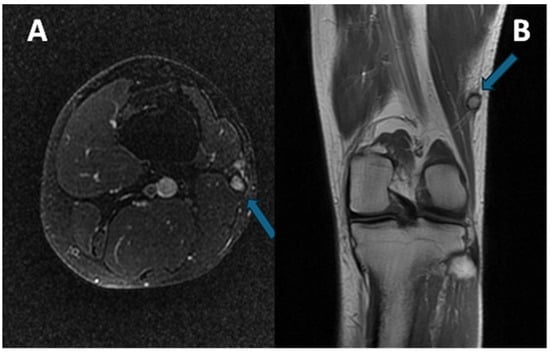

3.4. MRI Features

3.4.1. General MRI Features

3.4.2. Peritumoral Edema

3.4.3. Other MRI Features